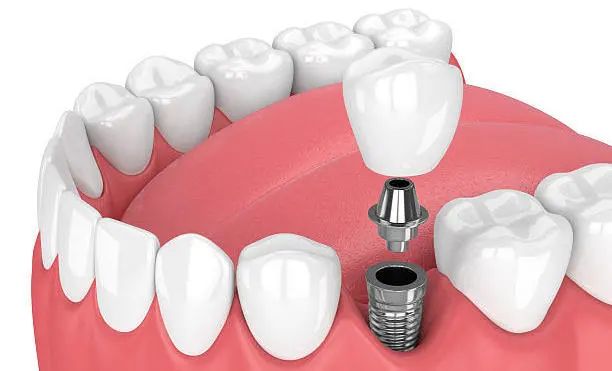

医生技术好 · 种牙不受罪 · 牙齿用到老 种植牙的成功与长久使用,与医生的医疗技术和水平及医院的设备有着直接的关系。那么由谁种,是种植牙成功的关键! 下面将从几个方面来看,如何选择一个好的种植医生。 一、看学历/资质 学历背景很重要,尽量选择口腔医学院校毕业的医学生,这些在专业口腔医学院校接受的培训和掌握的技术更规范和先进,水平较高的种植医生一般都是硕士、博士级别。 二、看进修背景 种植科医生会不断进修,一般选择口腔专科医院或是大型综合三甲医院口腔科或是国外的牙科学院进行进修学习 三、看种植技术,尤其是复杂种植完成质量 医生技术好,种植后就极少出现种植体与骨之间愈合不好而导致的牙松动、脱落等,越能把握种植牙长期效果,尤其是针对复杂牙种植后的完成质量,更是“一牙见分晓” 种植过程中,技术好的医生对种植体植入到牙槽骨的把握力度更好,对于基台穿龈的准确度就越高,为保证种植牙长久的使用打下良好基础 尤其是中老年人普遍面临着半口/全口缺牙、长期缺牙、牙槽骨萎缩吸收等难题,传统种植技术对老人身体损伤较大,导致无法实现种牙。而娴熟掌握先进技术的种植医生,能够做到少植骨或不植骨,更能保证种植后的效果和质量 四、看种植案例数量 种植牙是一项精细的医学手工技术,一般来说,临床经验越丰富,医生技术就会越好,种了100颗牙与种了10000颗牙的医生,在技术经验是有很大差别的,针对牙齿种植,所种植的数量越多,就能更好的帮患者患者减少种植过程中的手术痛苦、保证种植牙的长久使用 所以,选择医生一般都会选择种植经验丰富,这在很大程度上决定了种植牙后期的使用效果以及使用寿命 士嘉博士口腔医院舒适化种植团队 从种植体设计、生产,到医生把种植体植入牙槽骨,再到完成种植后患者的个人生活习惯,每一个环节、每一个细节都会影响种植体表面骨改建的动态平衡,继而影响种植成功还是失败。 因此,选择一个有经验有技术的种植医生尤为重要。 张士杰,山东大学口腔医学院博士研究生导师、教授、博士后,山东大学齐鲁医院口腔正畸科主任、主任医师。中华医学会口腔正畸专业委员会委员,中华医学会整形美容牙颌颜面美容分会常委,世界正畸联盟WFO会员。曾赴日本东京医科齿科大学、美国康州大学牙医学院、美国哈佛大学种植研修中心访问交流。发表学术论文四十余篇,其中被SCI收录十五篇,获山东省科技进步三等奖一项。承担国家自然科学基金、山东省自然科学基金、山东省科技攻关、山东大学自主创新、山东省重大专项等多项科研项目。口腔临床技能全面,以先进技术为基础、结合国外口腔诊疗服务理念,通过口腔正畸、种植修复、牙周治疗、牙齿美容等全面为患者提供适合的治疗方案,注重人文关怀。 擅长:成人及青少年各类牙齿畸形的矫正治疗,隐形矫正(山东省首批美国隐适美隐形矫正认证专家),在诊疗牙齿前突、开唇露齿、地包天、唇腭裂等正畸正颌联合手术治疗方面尤其突出,尤其擅长复杂牙列缺失的种植修复和咬合重建治疗。 高万郝,主治医师,山东大学口腔医学硕士,北京大学口腔医学院进修 擅长:各类牙齿种植、智齿拔除等口腔手术,熟练掌握多套国际先进的种植系统有多年口腔种植临床经验,尤其擅长复杂病例的咬合重建 病例分享一:77岁老人全口种植 父亲节当天,77岁的老人来士嘉博士口腔全口种植,老人得过脑梗、有心衰,本不想做牙齿上的治疗,在儿子坚持下做了种植,当天做到即刻拔牙即刻修复即刻全口种植,拔牙后吃上肉包子,由衷的感叹:香! 病例分享二:80岁奶奶上半口种植初体验 奶奶说“效果很好,牙齿很漂亮,一点都不痛!” 五、看选择的种植机构 口腔种植学,不仅是独立的学科,且涉及口腔颌面外科学、修复学、牙周病学、材料学、生物力学、影像学等口腔各学科领域。 先进的种植仪器 士嘉博士口腔医院坚持设备与国际同步,倡导舒适化的诊疗理念 我们引进了德国卡瓦3D数字化影像设备、德国3D瓷睿刻数字化牙椅旁修复系统、德国3D打印数字化种植导板系统、瑞士美国德国韩国等世界品牌种植系统等 能够提供当天就诊、当天戴牙,大大缩短了患者的等待时间。个性化服务更好,义齿生产质量更精密,还能快速解决临床戴牙所遇到的问题,更舒适、效率更高,客户满意度大大提高